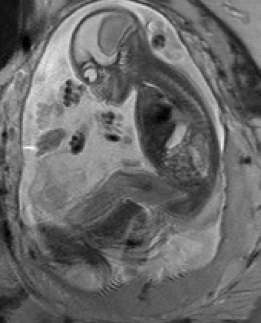

Reconstruction of Fetal Organs: Exemplary PVR and SVR reconstructions under motion introduced by kicking of the fetus are shown in Fig. 11. PVR reconstruction results show an improved visual appearance and less blurring in the region with severe motion artifacts (arrow). An example of a challenging clinical case with a kidney malformation in one of twin fetuses, is shown in Fig. 8. Our clinical partners confirmed that such complications are easier to examine and to quantify after PVR-based reconstruction.